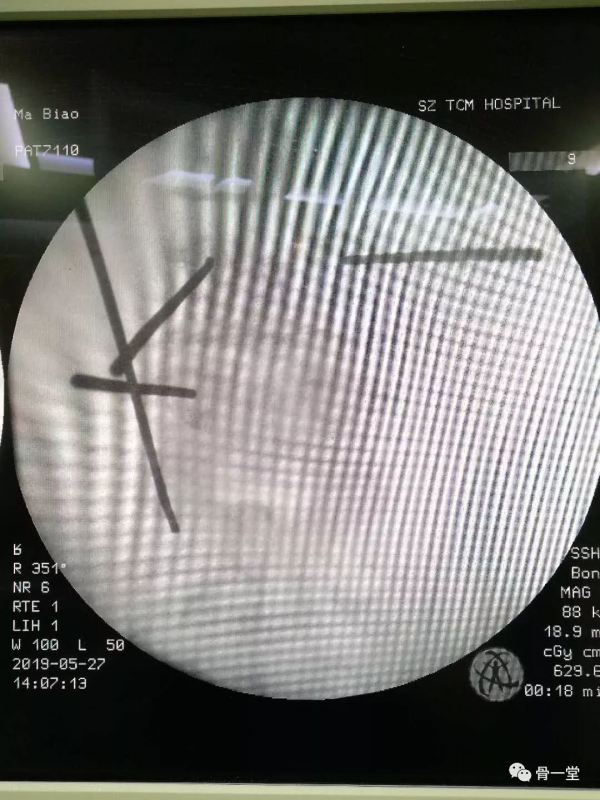

骨一科脊柱運動醫學學組團隊在蔣順琬教授的指導下經過術前充分準備,與患者詳細溝通後,微創手術如期進行。在麻醉科的密切配合下,術中採取小切口,打通工作通道,顯露突出的椎間盤,髓核摘除減壓後,準確植入融合器及釘棒系統,C型臂透視見各內固定器位置良好後,沖洗縫合切口,術中出血100ml,手術2.5小時,手術順利完成。術後第一天,患者下肢麻木厚重感就完全消失,感覺輕鬆,對前來查房的蔣順琬教授、馬篤軍主治醫師等連連感謝,術後第二天下地行走。現患者已治癒出院。

手術操作過程醫師站位